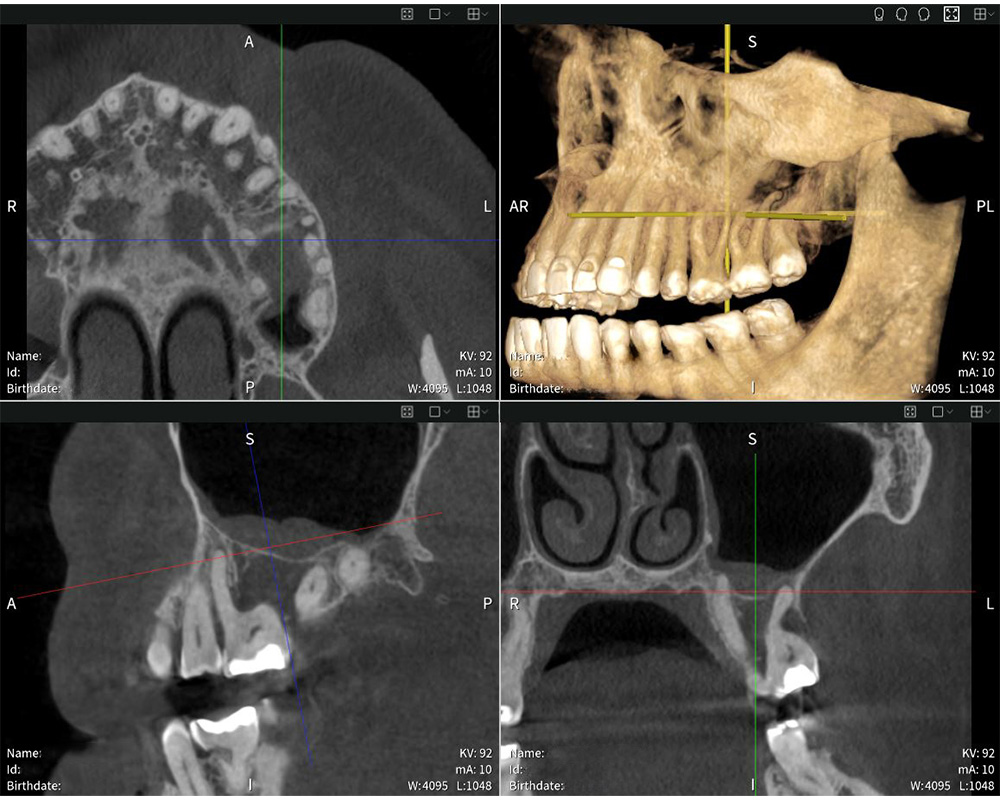

Präzise Bildgebung mit Seethrough Max: Das Röntgenbild zeigt die Schwellung der Schleimhaut im Sinus maxillaris.

Präzise Bildgebung mit Seethrough Max: Das Röntgenbild zeigt die Schwellung der Schleimhaut im Sinus maxillaris. © Dr med. dent. Mauro Amato